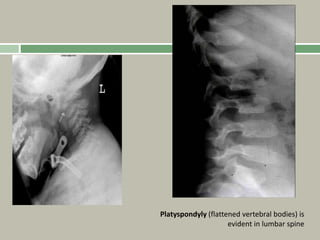

Spine

Platyspondyly, with anterior beaking and irregular

endplates,

Normal interpedicular distance

Odontoid hypoplasia

Atlantoaxial instability may be seen on flexion or

extension views.

Radiographic findings

Delayed appearance of the epiphyses (femoral heads

appear age 5 years),

Flattened irregular epiphyses,

Platyspondyly, possibly with a kyphoscoliosis,

Odontoid hypoplasia,

extension views,

Coxa vara, if severe, may result in femoral neck

discontinuity.

1, 2: Odontoid

hypoplasia and subtle anatomic axis

instability.

4:Pelvis, delayed ossification and irregular

epiphyses of the hips with overgrown

trochanters.

Fairbank’s triangle is present

3,5: Kyphoscoliosis with irregular vertebral

epiphyses.

Platyspondyly (flattened vertebral bodies) is

evident in lumbar spine